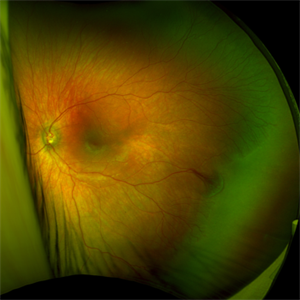

Fundus Photo of Closed Funnel Retinal Detachment

Wide-field funds photography of a closed funnel retinal detachment; patient had previously undergone 360 degree retinectomy in attempt to re-attach retina for a chronic retinal detachment, which was unsuccessful.

Condition/keywords: Closed funnel RD, detachment, Optos